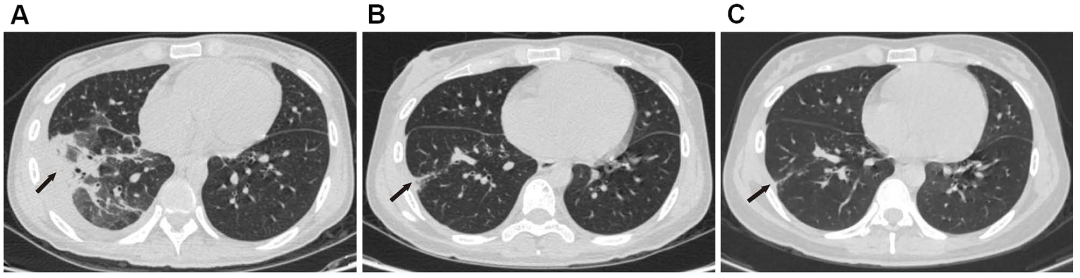

• 2020年5月和8月的胸部CT:肿大的肺门淋巴结已逐渐缩小(图 1B–E),且肺部病变明显吸收(图3A–C)

图3:(A)胸部CT显示斑片状浸润、带状和结节状阴影、胸腔积液。(A–C)右肺下叶病变,胸腔积液逐渐吸收。